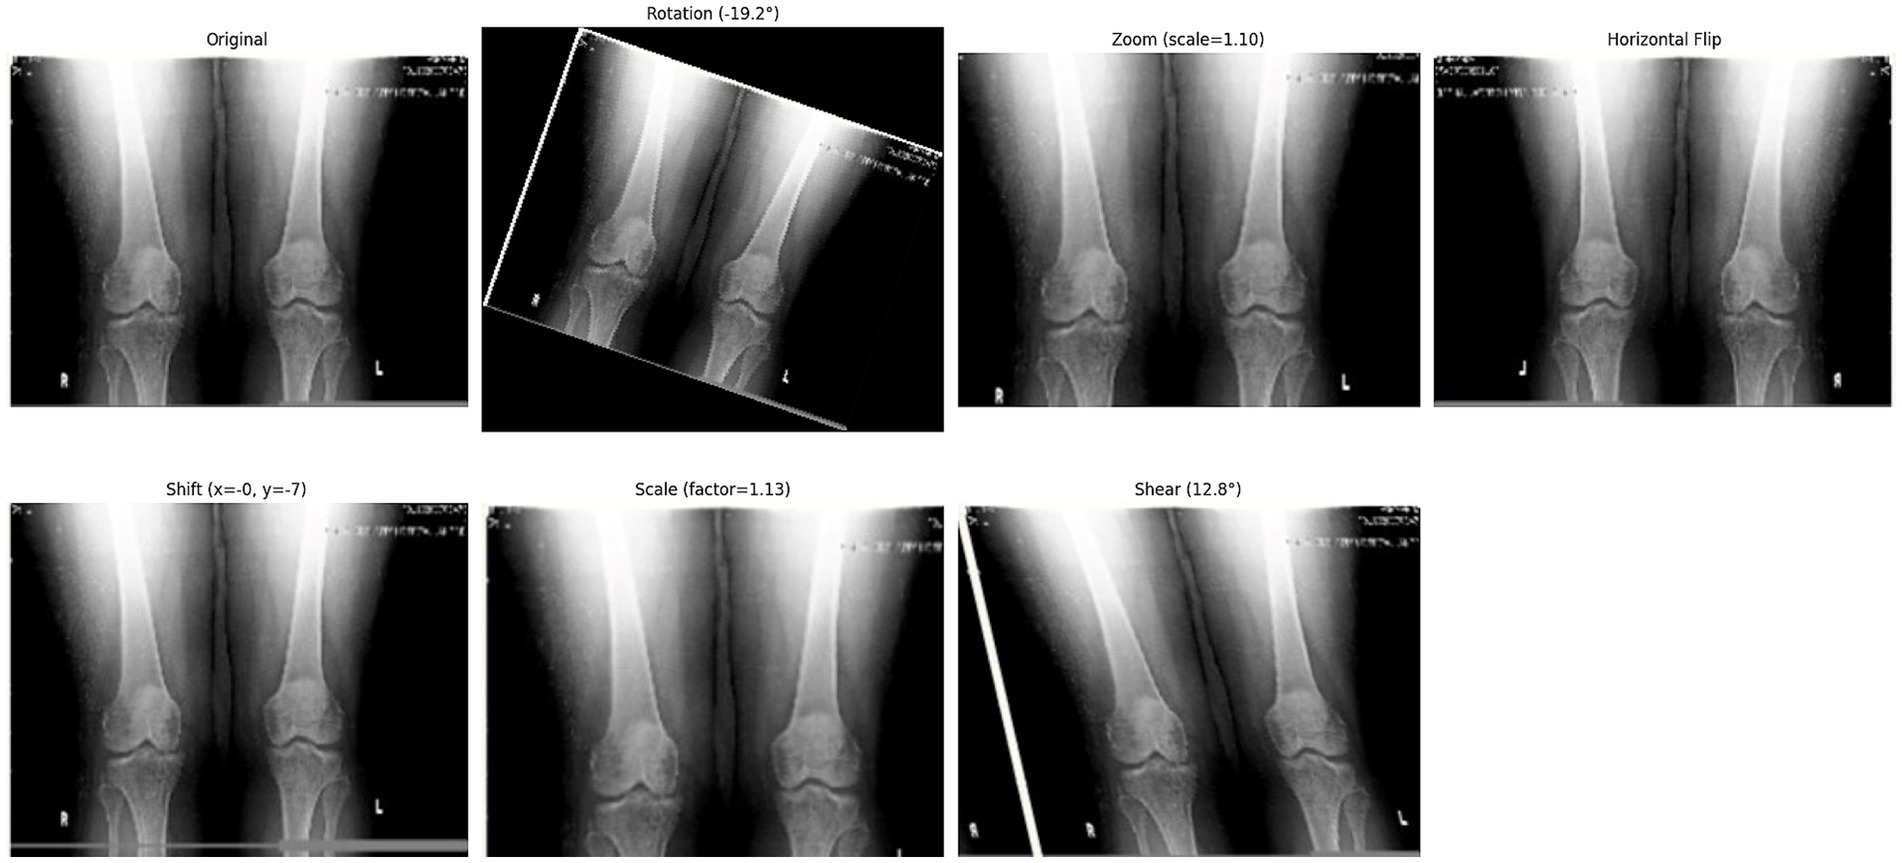

Following the completion of the pre-processing procedures, the dataset was divided into three separate sets: train, test, and validation. This partitioning was achieved via a two-step approach. Initially, 80% of the data was allocated for model training, with the remaining 20% (61 samples) designated for testing. In the subsequent phase, the training dataset underwent augmentation through rotation, zoom, and affine transformation techniques. Images were randomly rotated within a range of ±30 degrees to introduce rotational invariance. Zoom augmentation was applied by scaling images with a random factor between 0.8 and 1.2, enabling the model to handle variations in object size and perspective better. Additionally, affine transformations were employed, incorporating horizontal flipping, random shifts up to 10% of the image dimensions, scaling within the same 0.8–1.2 range, and shear angles up to ±20 degrees. Figure 6 shows the resulting images after applying different augmentation techniques to a sample image. The complete code for data augmentation is also given in 1. These parameters were chosen to increase dataset variability without distorting critical anatomical features relevant to KL grading. This augmented training dataset was further divided into 90% training and 10% validation. The number of training samples after data augmentation and testing sample (with no augmentation) per class is depicted in Figure 5.

Figure 6

X-ray images of knees with various transformations: original, rotated by negative 19.2 degrees, zoomed by scale 1.10, horizontally flipped, shifted (x=0, y=-7), scaled by factor 1.13, and sheared by 12.8 degrees.

Figure 6. Effect of different augmentation techniques on a sample image.